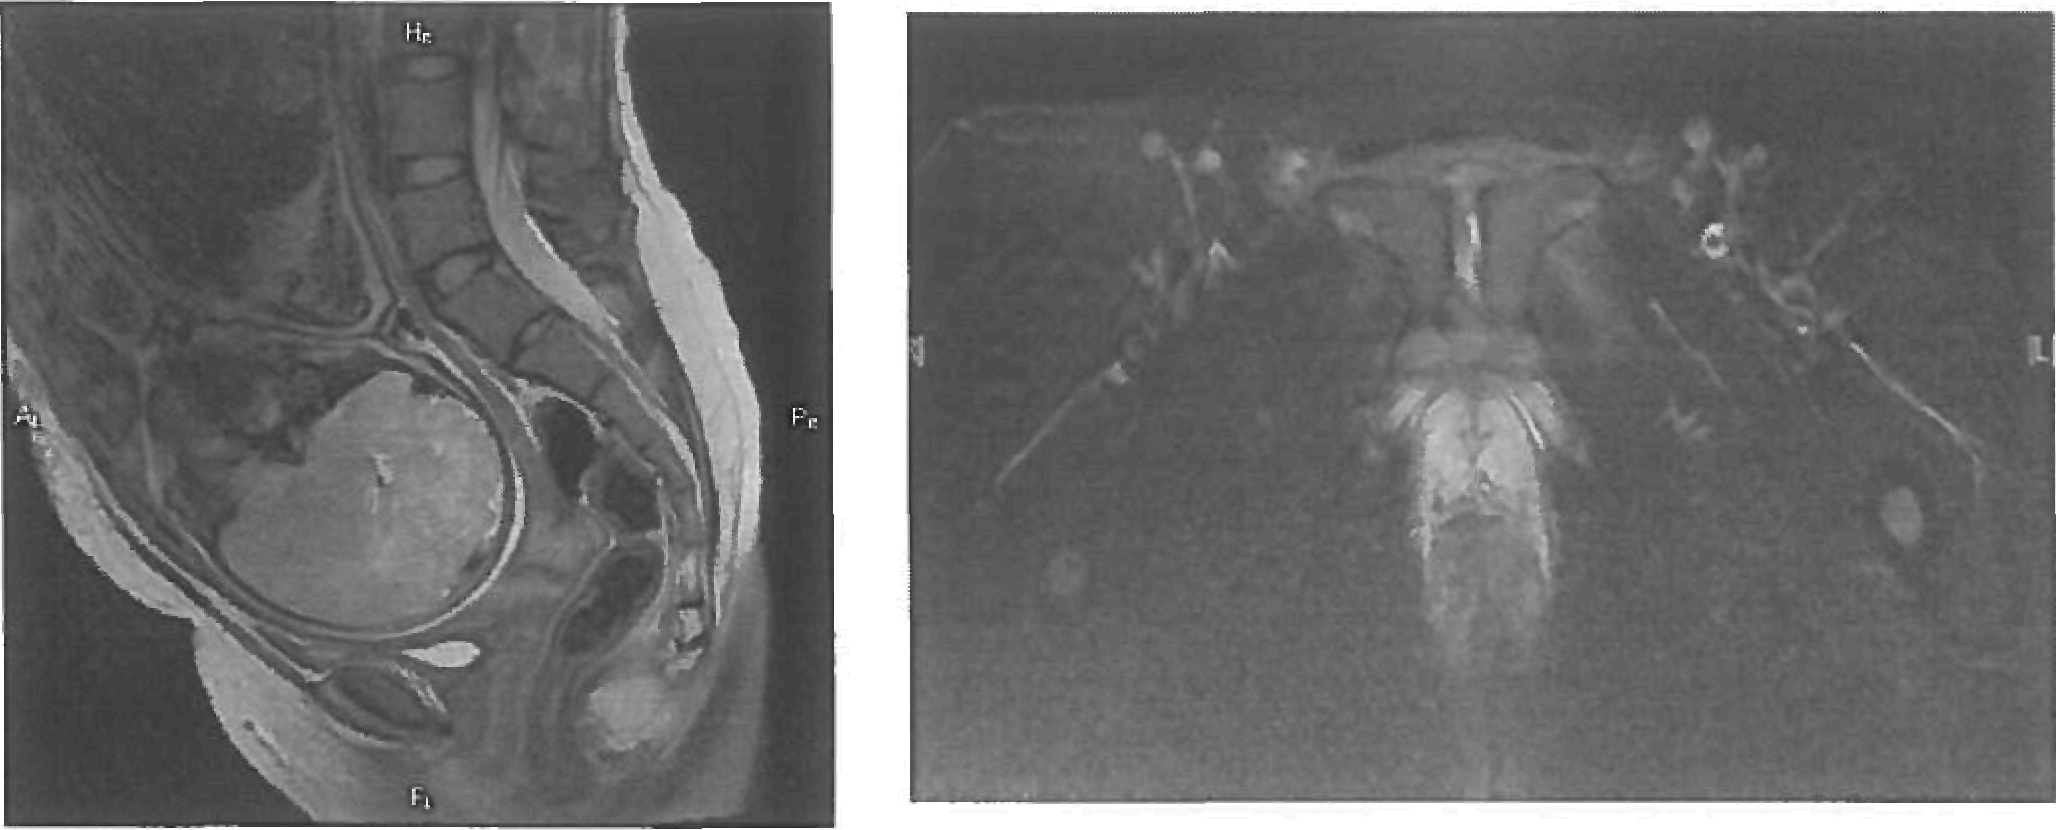

Рисунок 3. А. Т2ВИ в сагиттальной плоскости, пунктиром показана необходимая ориентация срезов для получения изображений по плоскости входа в таз. Б. Т2ВИ в сагиттальной плоскости, показаны основные размеры: 1 - широкой части, 2 - узкой части, 3 - выхода.

Рисунок 5. А - Т2ВИ в сагиттальной плоскости. Пунктиром показано планирование плоскости срезов для оценки состояния лобкового симфиза. Б - Т2ВИ с подавлением интенсивности МР-сигнала от жировой ткани через плоскость симфиза. Отмечается повышение интенсивности МР-сигнала от хряща, за счет явлений отека - признак симфизита